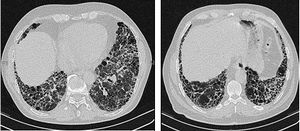

고해상 전산화 단층 촬영(HRCT)은 특발성 폐섬유증 진단에 가장 중요한 검사 방법 중 하나이다. HRCT에서 전형적인 통상적 간질성 폐렴(UIP) 소견, 즉 양쪽 폐 기저부와 흉막 하부에 뚜렷한 벌집 폐 소견을 동반하는 망상 음영과 미세한 유리 음영이 확인되면 수술적 폐 생검 없이 IPF로 진단할 수 있다.[3]

HRCT에서 전형적인 UIP 패턴이 보이지 않는 경우, 확진을 위해 개흉술 또는 흉강경 검사를 통한 외과적 폐 생검이 필요할 수 있다.[3] IPF 환자의 폐 조직은 특징적인 조직 병리학적 UIP 패턴을 보이며, 주요 특징은 '패치워크 패턴'의 간질 섬유증, 간질 흉터, 벌집 변화 및 섬유아세포 초점이다.

특발성 폐섬유증(IPF) 급성 악화는 30일 이내에 설명되지 않는 호흡 곤란의 악화 또는 발생과 함께, 고해상도 흉부 컴퓨터 단층 촬영(HRCT)에서 새로운 방사선학적 침윤이 나타나는 것으로 정의된다. 이는 종종 UIP 패턴과 일치하는 배경에 겹쳐 나타난다. 연간 발생률은 전체 환자의 10~15% 사이이다. 예후는 좋지 않으며, 사망률은 78%에서 96%에 이른다.[64] 폐색전증, 울혈성 심부전, 기흉 또는 감염과 같은 다른 원인은 배제해야 한다. 폐 감염은 기관 내 흡인물 또는 기관지 폐포 세척(BAL)을 통해 배제해야 한다.급성 악화를 경험하는 많은 환자는 집중 치료가 필요하다.[65] 특히 호흡 부전이 혈역학적 불안정, 유의미한 동반 질환 또는 심한 저산소혈증과 관련된 경우에 그러하다. 그러나 입원 중 사망률이 높다.[64] 기계 환기는 개인의 장기적인 예후와 가능한 경우 개인의 희망을 신중하게 고려한 후에 도입해야 한다. 현재 지침은 특발성 폐섬유증으로 인한 호흡 부전 환자에서 기계 환기 사용을 권장하지 않는다.[3]